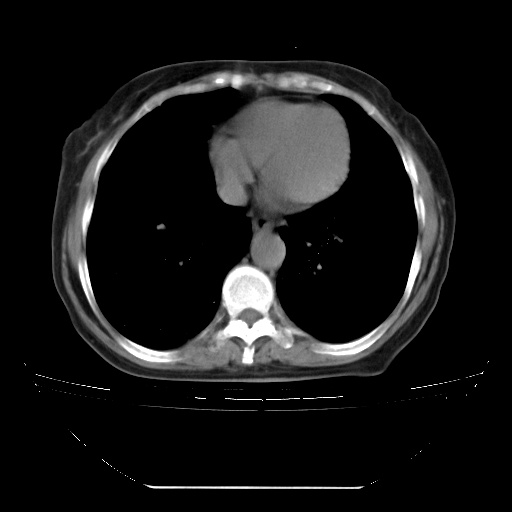

患者女性,72岁,慢性咳嗽3月余,曾抗炎治疗无效果,最近抗结核治疗约半月余,症状缓解。

ct示两肺粟粒状病灶,以两肺上叶尖后段及下叶背段分布为主;首先考虑结核。请战友们分析。

查原发灶吧,肺内转移瘤!肝内也有病灶,需强化明确。

两肺内病灶呈小结节状和树芽状,纵膈的肿大的淋巴结密度不均匀,并见有钙化,考虑为两肺结核可能更大些。

两肺内病灶呈小结节状和树芽状,纵膈的肿大的淋巴结密度不均匀,并见有钙化,多形态病灶,考虑为两肺结核,肝内考虑小囊肿。

纵隔见肿大淋巴结并钙化,首先考虑结核,但感觉小结节像“挂果”征,分布位于支气管边缘,所以不排外肺泡癌,建议抗唠后复查吧?不然是癌的话,也不好治吧?化疗?